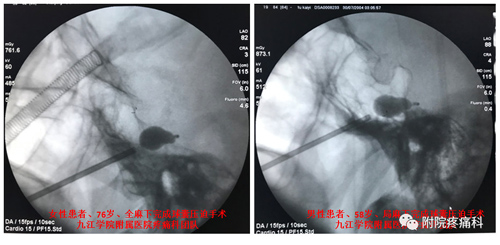

近日,临床医学院/附属医院疼痛科成功为多例顽固性三叉神经痛患者实行一种全新的微创手术——三叉神经球囊压迫术,这也标志着该院疼痛科熟练掌握该项技术并走在省内前沿。今后,九江及周边地区三叉神经痛患者不出远门,不开刀,仅通过面部一个针眼和数分钟操作,即可快速治愈、快速出院。

三叉神经球囊压迫术手术方法简单,在X线透视监视下,将一个微球囊导入Meckle’s腔的三叉神经的半月节,然后缓慢注入对比造影剂充盈球囊,把导致三叉神经痛的神经纤维解除卡压、并通过扩张的微球囊压迫破坏,最后退出球囊,拔出穿刺针。术中病人耐受性良好,在全麻下接受整个手术,没有疼痛和不适感,伤口小(针眼大小), 手术时间短,术后疼痛立即缓解率可高达95%以上, 当天即可下床活动,基本不影响术后进食,并发症发生低。该手术适应症广,除了原有射频热凝术的适应症,对原发性三叉神经第一支疼痛、射频热凝术后效果欠佳的病人都有效,具有综合其它手术的优点:微创、安全、有效、风险小、不易复发。该手术因人性化、舒适度高、恢复快、病人接受度高,在欧美发达国家已广泛开展。